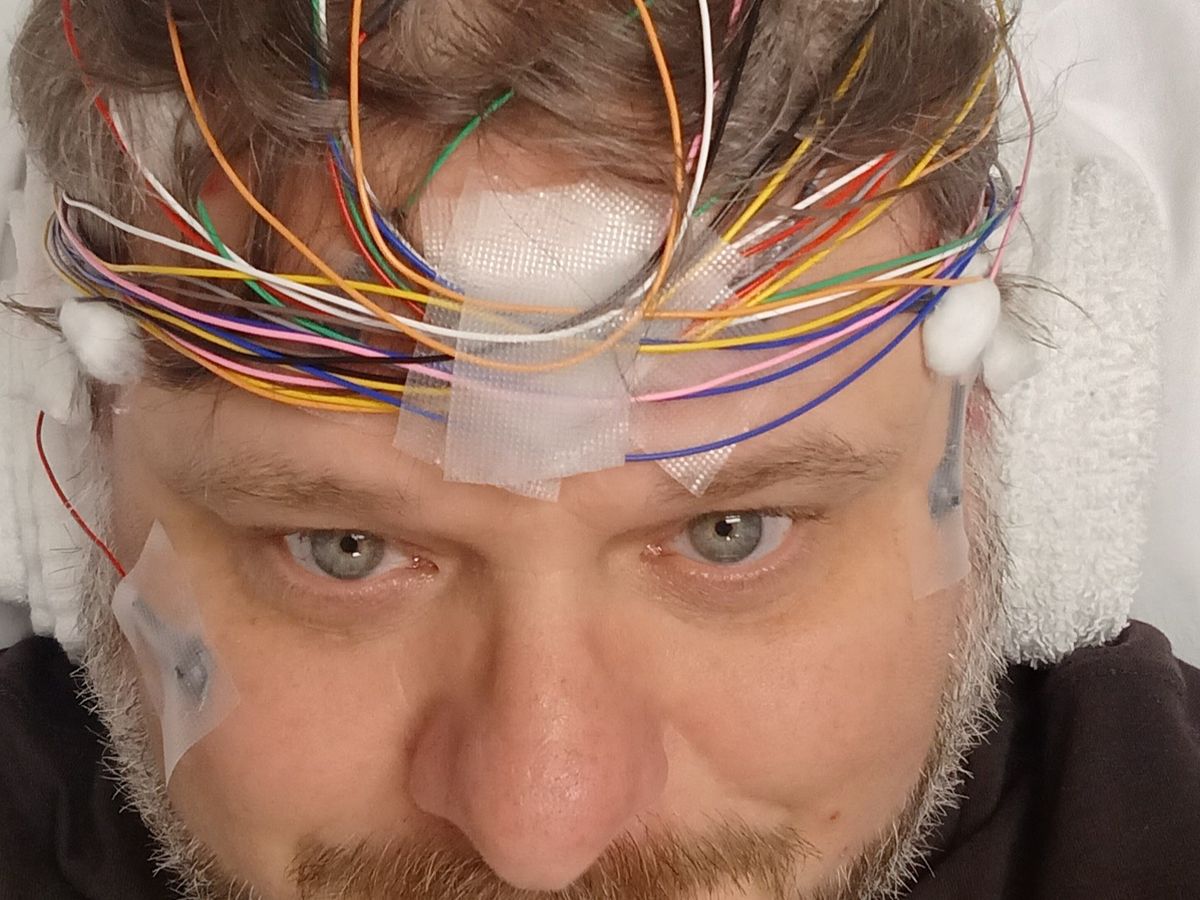

Hi, my name is Shaun. I’ve spent my life working hard as a Painter, providing for my family with my own two hands. I never imagined that my health would collapse the way it has. Over the past few years, my medical situation has become extremely complex. I’ve developed autoimmune arthritis, intermittent loss of leg function, chronic pain, severe fatigue, and memory problems linked to a micro-hemorrhage in my brain. On top of that, I lost leg function due to a failed knee replacement and a failed knee revision, which also caused a deep vein thrombosis (DVT). These conditions have taken away my ability to work, even though I’ve tried to push through as long as I could.